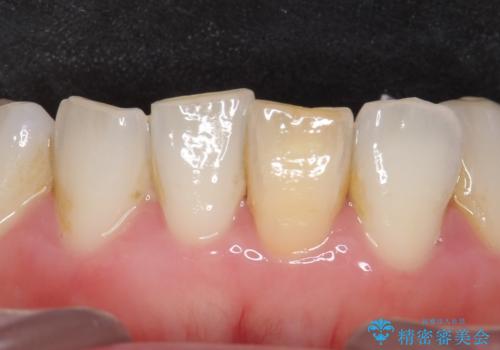

インプラント治療により、周りの歯を削ることなく咬合を回復することができました。